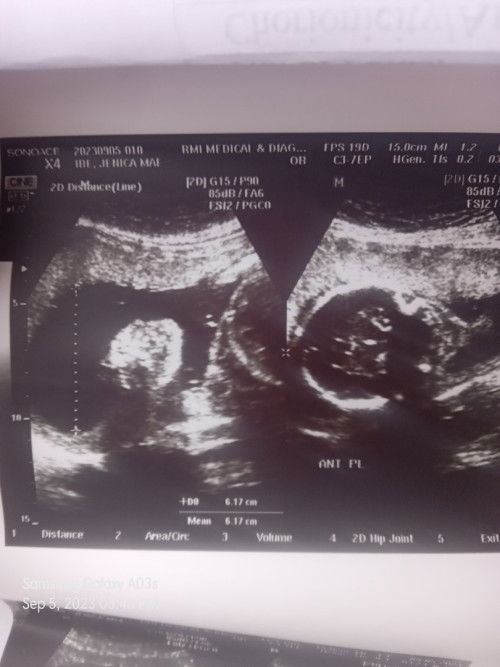

Sa tingin nyo po ano gender sabi kse 50% bbgurl

Ultrasound

#36weeks1day